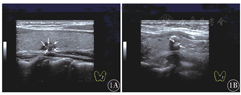

超声声像图显示,点状钙化组钙化灶呈低回声结节内点状强回声,散在分布,不伴声影和"彗星尾征"(图1A);片状钙化组钙化灶呈斑片状分布,位于结节边缘或中央,位于边缘可呈弧形,中央可呈簇状,常伴声影(图1B)。